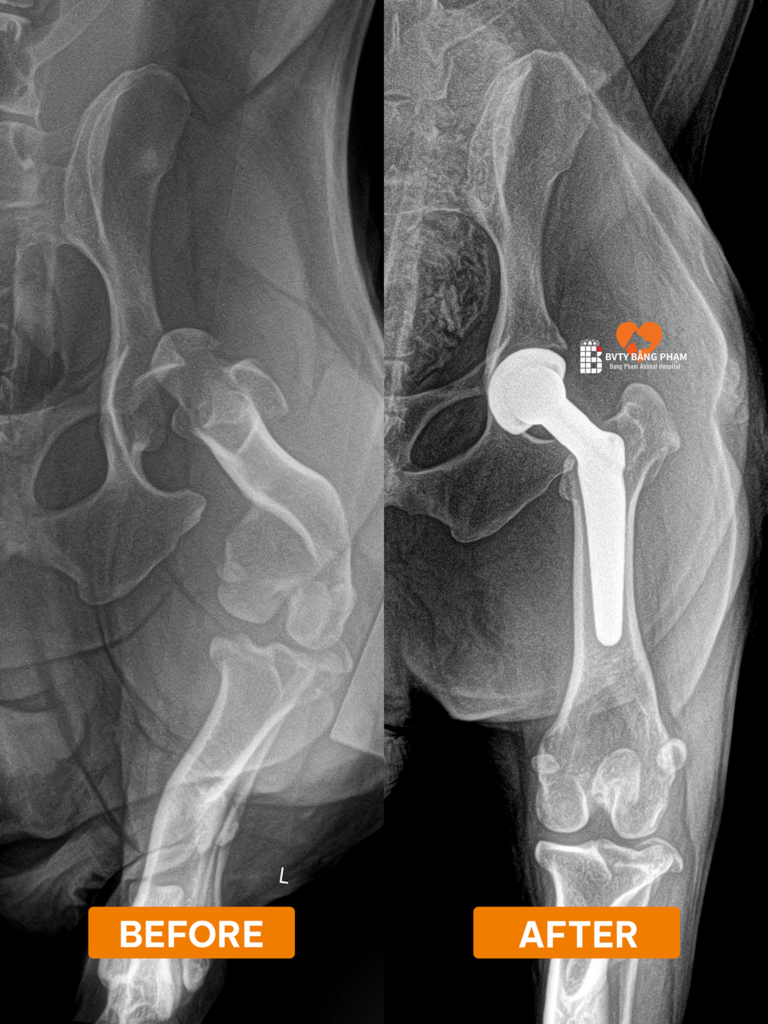

thay khớp háng nhân tạo chó mèo

Nếu kết quả chụp phim cho thấy bé bị gãy xương, đứt dây chằng hay thoái hóa khớp háng nặng, các phương pháp nắn bóp thông thường sẽ không có tác dụng. Lúc này, DỊCH VỤ THAY KHỚP HÁNG THR chính là giải pháp dứt điểm, giúp bé lấy lại những bước chạy nhảy vui vẻ như ngày đầu.